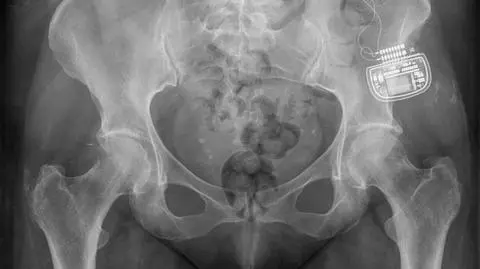

Urządzenie wszczepione w ciało pacjentki

Źródło: Marcin Walczak | TVN24 Wrocław

- To rozwiązanie jest o wiele wygodniejsze – zachwala pani Ewa. – Wystarczy, że ładowarkę podepnę do prądu. Średnio na 40 minut. Potem wyłączam urządzenie z prądu, ładowarkę z antenką przykładam do miejsca, gdzie znajduje się bateria i po prostu się ładuję – wyjaśnia z uśmiechem. – W środku jestem cała okablowana, na zdjęciu rentgenowskim wyglądam trochę jak robot – żartuje pacjentka.